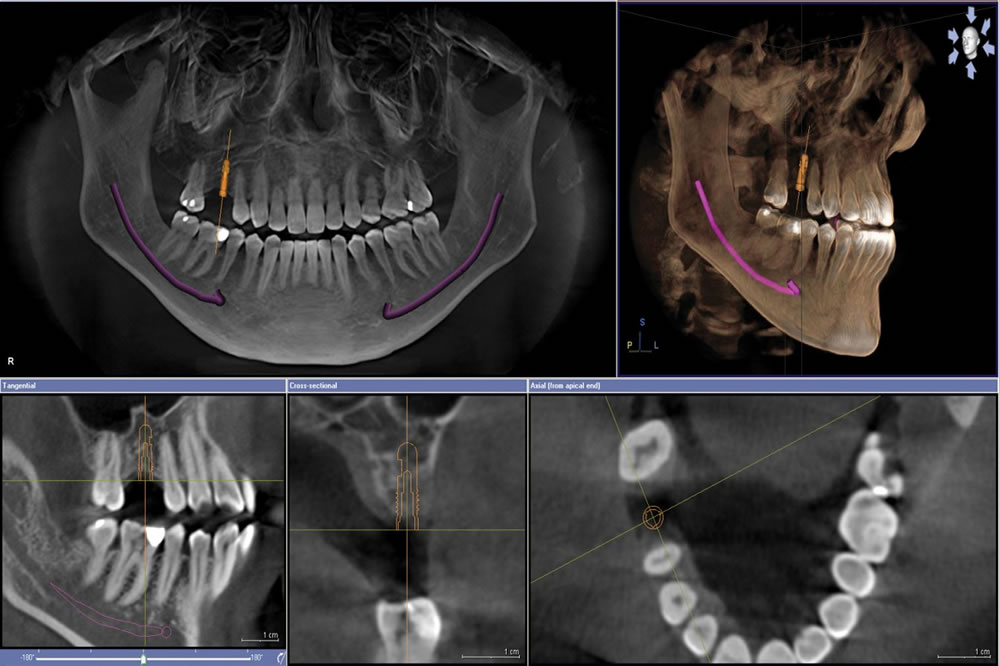

本日来院されたO様、ご自身のお口の現状を詳しく知りたいということで、「歯科ドック」を受けて頂きました。検査により、ご自身ではほぼ気になる症状が無かったようですが、鼻にまで広がる大きな病巣が見つかりました。通常の検診で行うレントゲン検査では見つけることが出来ませんので今回の検査で、早い段階で治療を進める事ができると思います。

CTのお陰ですね!!